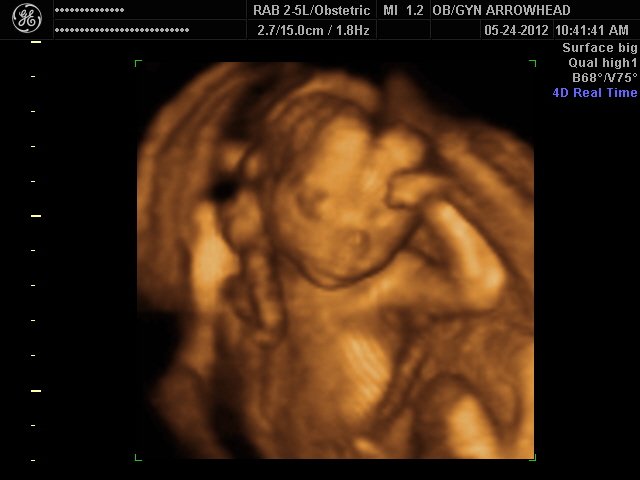

We offer complimentary 3D/4D Ultrasounds to all our OB patients around 30 weeks! The following photos are some examples of our work, shown with permission from our patients.